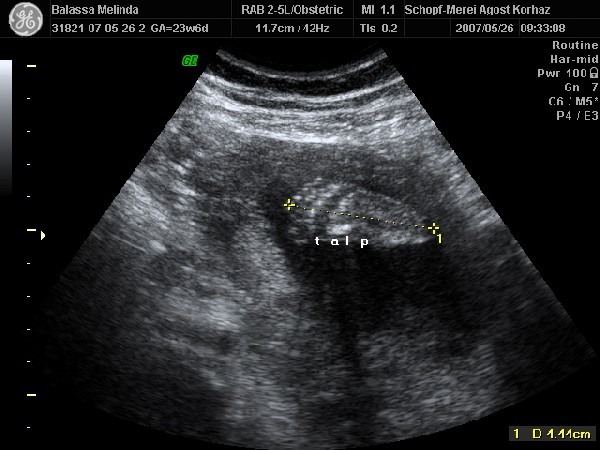

Mi volt az uh-n?